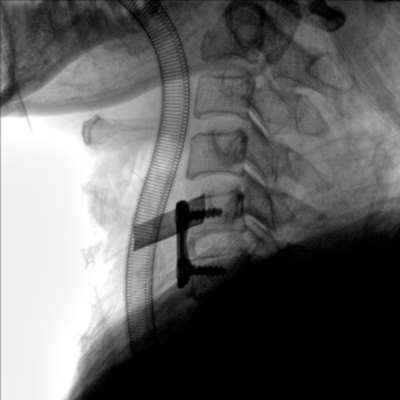

大尺寸動(dòng)態(tài)平板探測器,高DQE、低噪聲、圖像清晰。采用多分辨率圖像增強處理技術(shù),不同部位不同圖像處理算法,滿(mǎn)足客戶(hù)多樣化的需求。

采用智能變頻脈沖透視技術(shù),優(yōu)化圖像質(zhì)量的同時(shí)降低輻射劑量,呵護醫患健康

多角度自由旋轉,滿(mǎn)足患者復雜擺位需求。